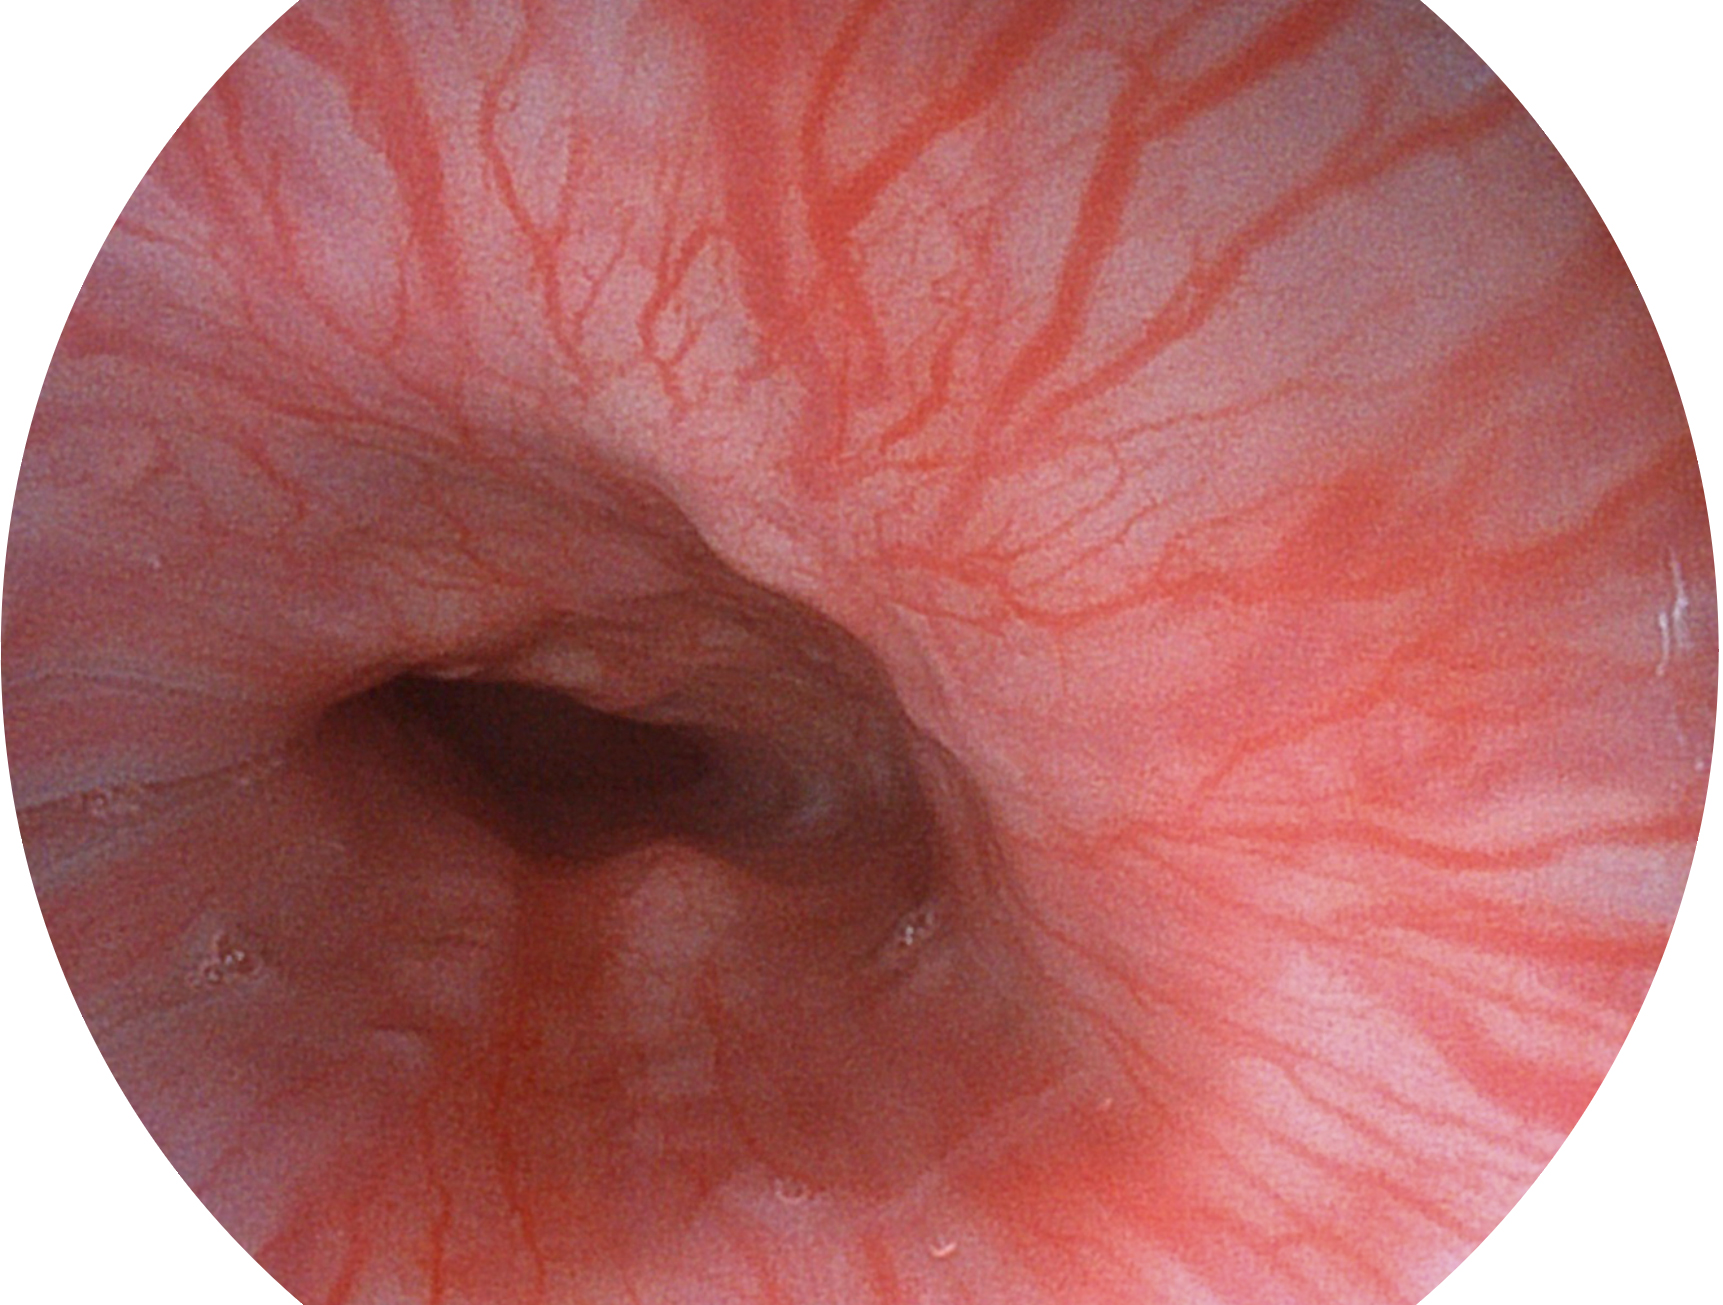

SFI技术是结合特定光谱照明与数字光谱滤波,实现高亮度特殊光成像。染色模式下,不改变粘液、食物残渣、粪液等基本颜色,在保持与白光照明相似的图像色调的同时突显了图像颜色的红白对比度,且在远距离观察的情况下具备与普通白光模式相同的图像亮度,有助于消化道疾病的大范围扫查和早癌筛查。

• 白光图像 SFI图像